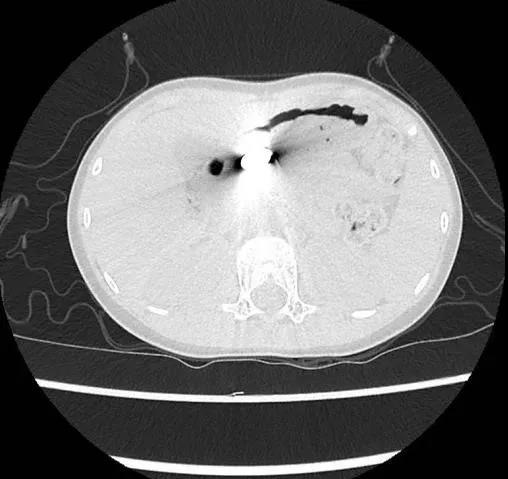

家长慌乱用手机搜索处理方法,甚至还按照网上偏方让小逸吃了一把韭菜企图促进排出。吃完后,小逸的腹胀不适反而加重。父母这才赶紧把小逸送到中山大学附属第六医院急诊就诊。经过CT检查,发现磁铁已进入胃部。急诊医生马上联系该院内镜外科,希望为患儿通过胃镜取出磁铁。

CT显示磁铁已进入胃部。